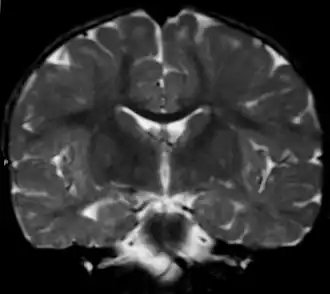

| Вид фронтального среза головного мозга при метахроматической лейкодистрофии (МРТ). | |